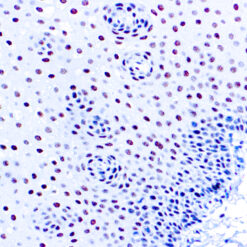

Cytokeratin (CAM5.2)

Anti-Cytokeratin (CAM 5.2) reagent has a primary reactivity with human keratin proteins that correspond to Moll’s peptides #7 and #8, Mr 48 and 52 kilodaltons (kd), respectively. Cytokeratin 7 and 8 are present on secretory epithelia of normal human tissue but not onstratified squamous epithelium. Anti-Cytokeratin (CAM 5.2) stains most epithelial-derived tissue, including liver, renal tubular epithelium, and hepatocellular and renal cell carcinomas. Anti-Cytokeratin (CAM 5.2) might not react with some squamous cell carcinomas.

| Cellular Localization | Cytoplasmic |

| Pretreatment | Citrate Buffer pH 6.0 |